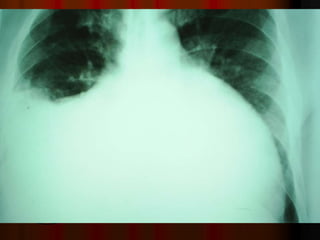

Рентгенография

Рентгенография грудной клетки

иногда выявляет расширение границ

сердца и/или признаки застоя в легких